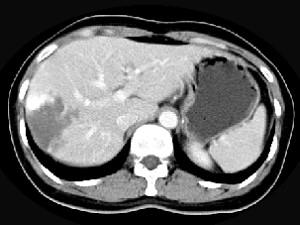

问题 女,38岁,无任何症状,体检发现肝右叶占位性病变,增强表现如图,最可能的诊断为 ( )

选项 A、肝脓肿 B、肝腺瘤 C、肝转移瘤 D、肝血管瘤 E、原发性肝癌

答案 D